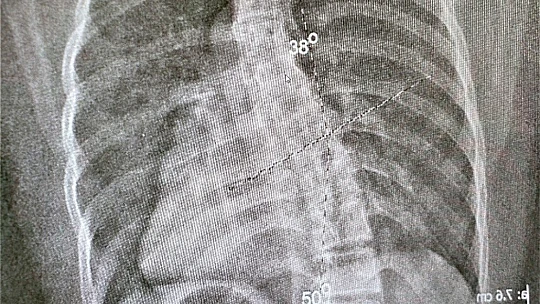

Skolyoz hastalığı ve belirtileri hakkında bilgi veren Fizyoterapist Muhammed Barış, “ Skolyoz, omurgada üç boyutta meydana gelen eğrilmelerin oluşturduğu bir deformitedir. Çok net bir şekilde evde yapılabilecek basit testlerle bu hastalığın varlığını anlayabiliyoruz. En çok hitap ettiğimiz, lise ve ortaokul grubu çocuklardır. Çünkü bu yaşta fark edildiği zaman skolyozun tedavisinde daha etkin sonuçlar alabiliyoruz. Özellikle çıplak bir şekilde çocuğunuza arkadan baktığınız zaman kürek kemiklerinde biri diğerine oranla biraz daha aşağıda duruyorsa,omuz boylarında eşitsizlik varsa, daha aşağı geldiğimiz zaman kalçada da bir eşitsizlik varsa bizlere başvurmalarını öneriyoruz. Bize en çok ‘bir bacağım diğerine göre daha kısa hissediyorum,nefes alırken kaburgalarım bana batıyor,bir omuzum diğerine oranla daha aşağıda yada aynadan baktığımda iki tarafım eşit değil’ gibi şikayetler ile geliyorlar. Bu şikayetlerle gelen hastalarımızı ilgili birimlerin uzman hekimlerine yönlendiriyoruz.Skolyoz tanıları alındıktan sonra fizik tedavi biriminde seanslarımıza başlıyoruz” dedi.

Skolyoz hastalığının istatistiksel verilerini paylaşan Barış“ Yapılan çalışmalarda bu hastalık grubunda yüzde 2 ile 4 arasında bir oran var. Yani 100 kişiden 2’si veya 4’ü skolyoz hastası. Bunun büyük bir kısmı bu deformitenin farkında değil. Kız çocuklarında erkek çocuklarına oranla 8-10 kat daha fazla gözüküyor. Burada bizim için en önemli olan şey, kız çocuklarında menarj döneminde büyüme hormonu daha fazla salgıladığı için omurgada uzama meydana geliyor.Meydana gelen bu uzama mevcut skolyoz açısının artmasına sebebiyet veriyor. Skolyoz hastası bir kız çocuğunun mutlaka ilk reglinden hemen sonra bir fizyoterapiste danışması gerekiyor. Ondan sonraki 6 ay ile 2 senelik dönemde mutlaka kontrolümüzde olması gerekiyor” diye konuştu.